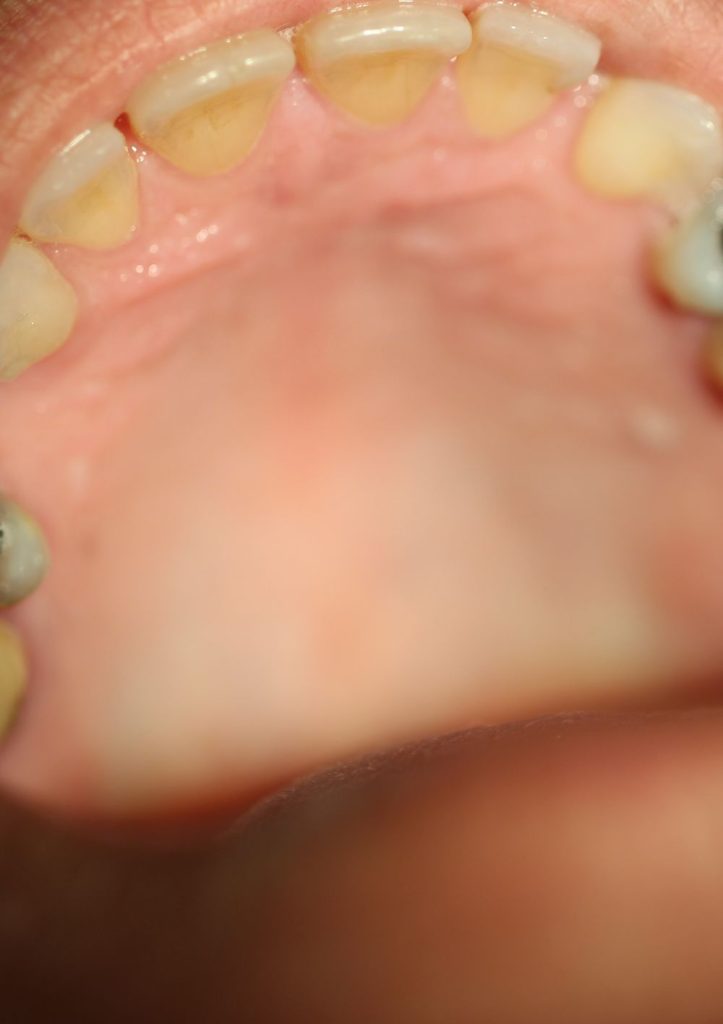

Σε video καταγράφεται σε θήλυ ασθενή εκτεταμένη βλάβη επουλίδας fissuratum στα ούλα της άνω γνάθου, η οποία αφαιρέθηκε με τη χρήση ηλεκτροτόμου SERVOTOME. Μετά από διάστημα 6 εβδομάδων, η ασθενής προσήλθε για επανεξέταση και διαπιστώθηκε, όπως φαίνεται και στη φωτογραφία, η πλήρης επούλωση στην περιοχή.

Επούλωση της βλάβης 6 εβδομάδες μετά τη χειρουργική αφαίρεση της βλάβης

Αρχική κλινική εικόνα βλάβης

Χειρουργική αφαίρεση βλάβης

Επούλωση βλάβης 7 ημέρες μετά τη χειρουργική αφαίρεση της βλάβης

Tελικη εικόνα μετά την αφαίρεση της βλάβης